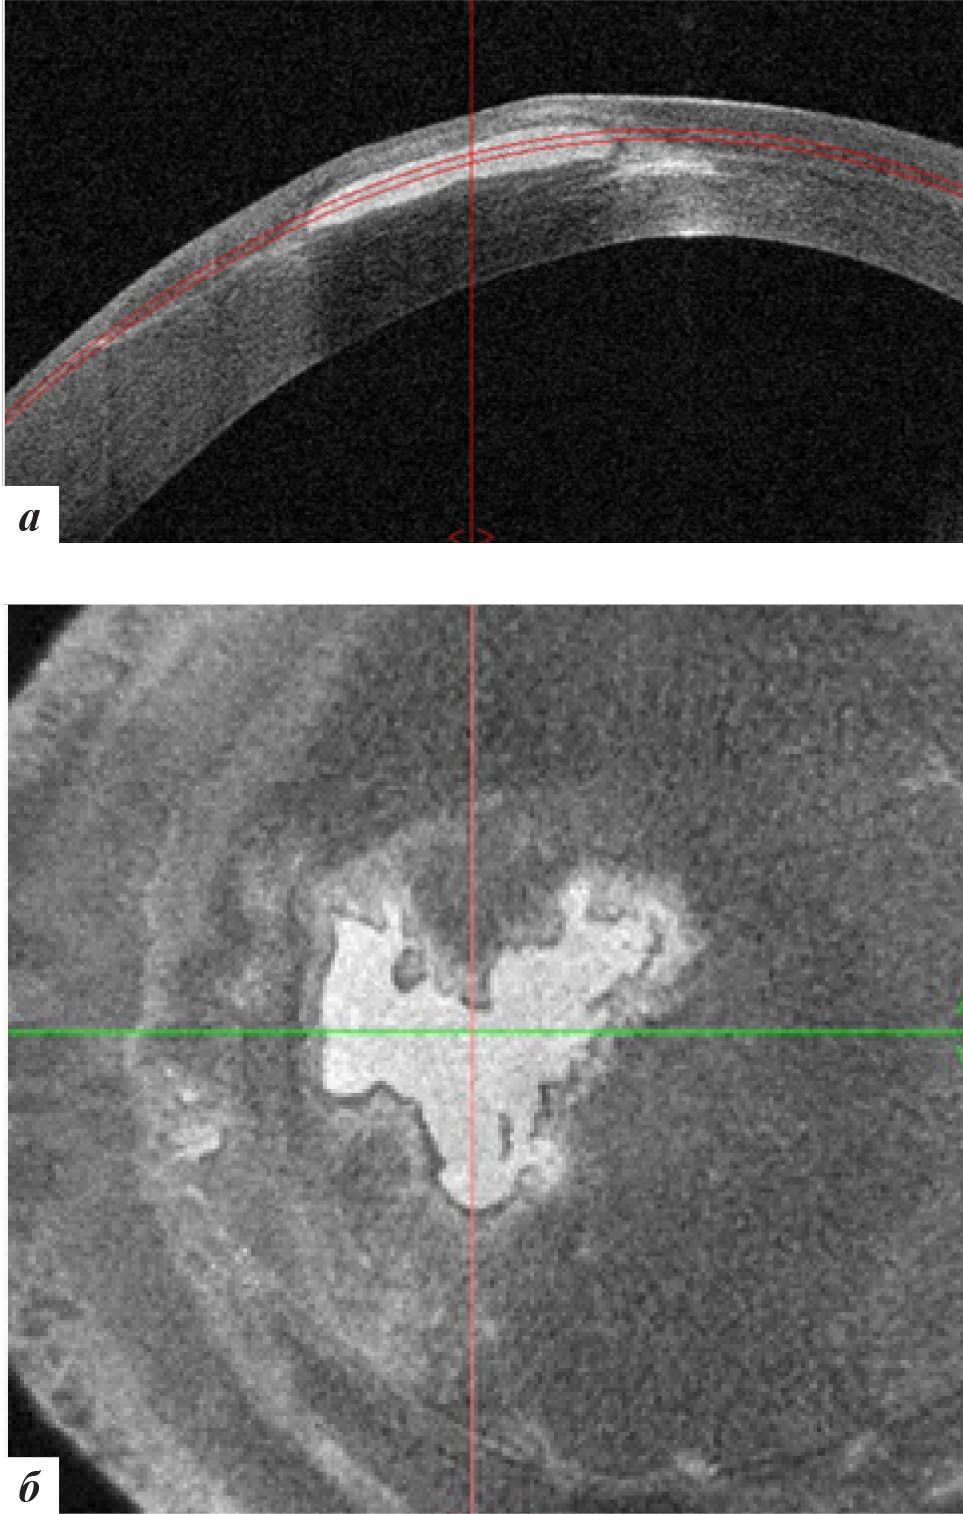

При офтальмобиомикроскопии глаз спокоен, в роговичном интерфейсе в ЦОЗ и параоптической зоне отмечена элиминация эпителиальных клеток с формированием стойких облаковидных помутнений (рис. 8) с отсутствием перифокального отека. ОКТ-сканирование передней поверхности роговицы также подтвердило отсутствие признаков рецидива врастания (рис. 9). С рекомендациями использования слезозаменителей пациентка выписана по месту жительства.

Рис. 9. Данные ОКТ роговицы левого глаза через 9 месяцев после лечения: а – горизонтальная проекция, б – фронтальная проекция